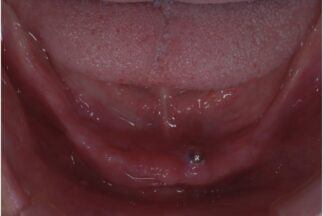

初診時の下顎咬合面観

-